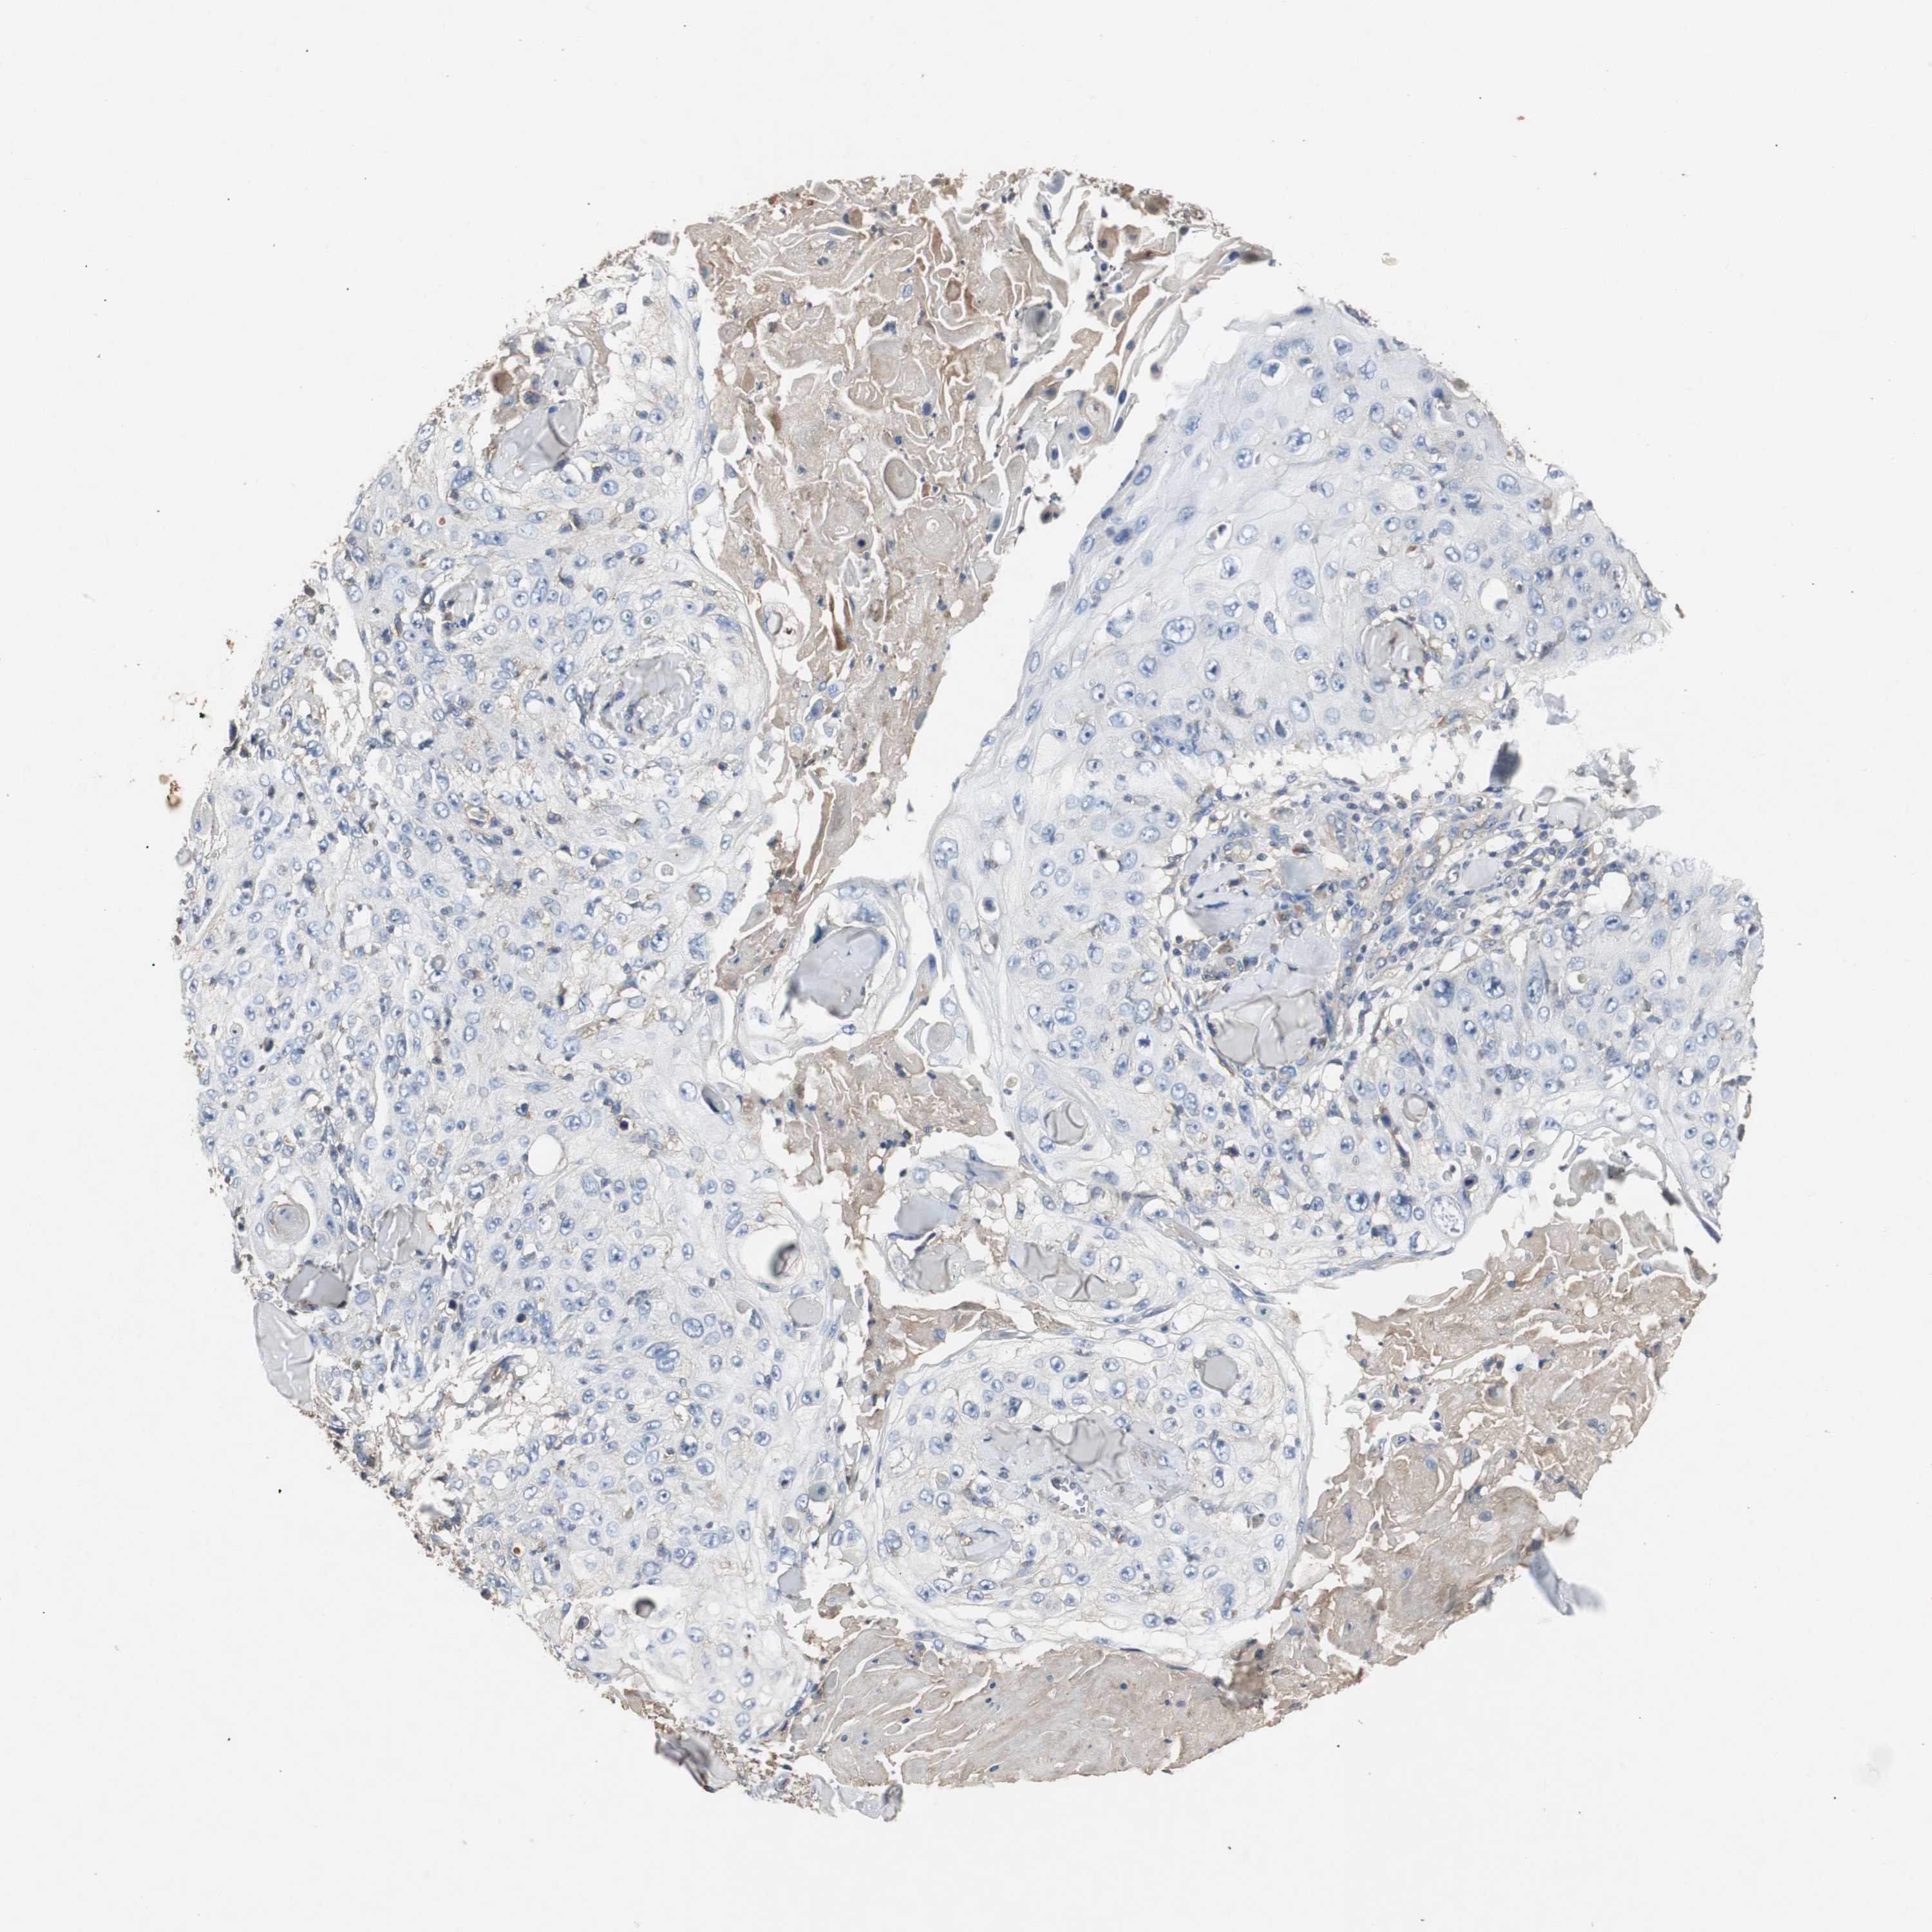

SKIN CANCER - Protein expressioni

A mouse-over function shows sample information and annotation data. Click on an image to view it in a full screen mode. Samples can be filtered based on level of antibody staining by selecting one or several of the following categories: high, medium, low and not detected. The assay and annotation is described here.

Antibody stainingi

Antibody staining in the annotated cell types in the current human tissue is reported as not detected, low, medium, or high, based on conventional immunohistochemistry profiling in selected tissues. This score is based on the combination of the staining intensity and fraction of stained cells.

Each image is clickable and will lead to virtual microscopy that enables deeper exploration of all samples and also displays staining intensity scores, fraction scores and subcellular localization as well as patient and tissue information for each sample.

Antibody HPA006404

Squamous cell carcinoma, NOS